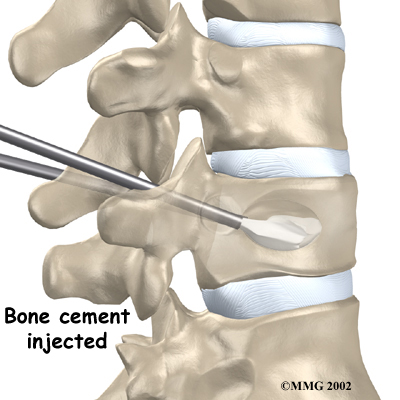

Vertebroplasty

This procedure is most helpful for reducing pain. It also strengthens the fractured bone, enabling patients to rehabilitate faster.

To perform vertebroplasty, the surgeon uses a fluoroscope to guide a needle into the fractured vertebral body. A fluoroscope is a special X-ray television that allows the surgeon to see your spine and the needle as it moves. Once the surgeon is sure the needle is in the right place, bone cement, called polymethylmethacrylate (PMMA), is injected through the needle into the fractured vertebra. A reaction in the cement causes it to harden within 15 minutes. This fixes the bone so that it does not collapse any further as it heals. More than 80 percent of patients get immediate pain relief with this procedure.

Iron City Physical Therapy's Guide to Vertebroplasty